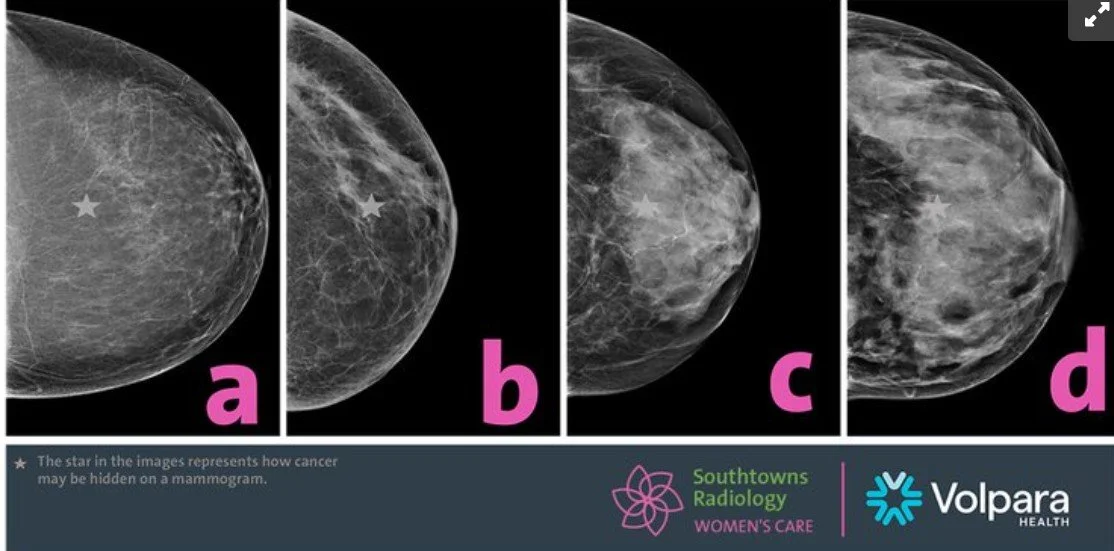

Prof John Wolfe in the 1970s started relating how the breast looks on an x-ray to future breast cancer risk, but for various reasons the field fell into disrepute until Prof Norman Boyd (with many colleagues) started showing repeatable results from a semi-automated measurement of breast density versus risk. The work in my PhD and then at Volpara led to a way to automate, in a quantitative way, the measurement of breast density, “volumetric breast density”. The sheer mass of evidence around breast density and risk (in its various forms), and the demands from women like Dr Nancy Capello to know that information led ultimately to the FDA in the US requiring that all women screened should be told their breast density from Sept 2024 - some 50 years post John Wolfe’s initial thinking.

In the picture you’ll see four images of different density breasts - can you see the white star? That is the “masking risk” of breast density, it’s also an independent risk factor for development of breast cancer.